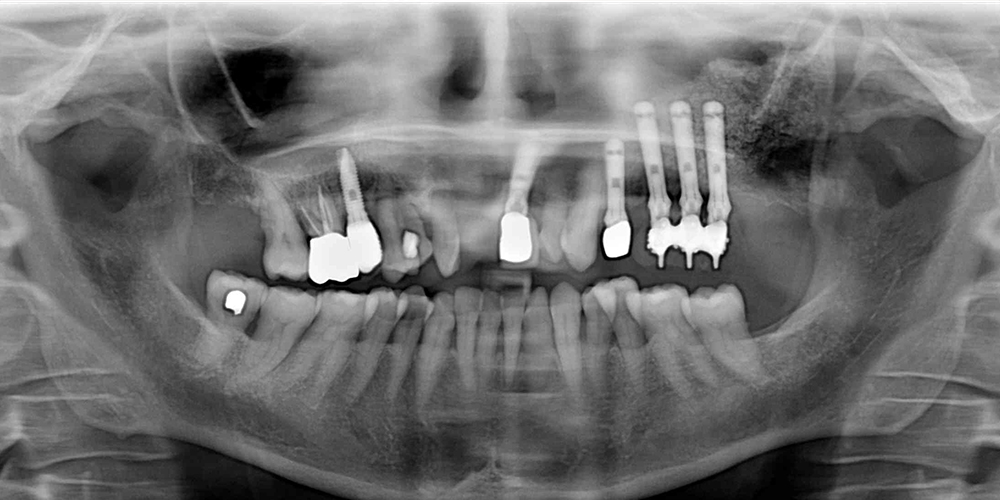

Quando i denti posteriori dell’arcata superiore vengono estratti, il pavimento del seno tende ad abbassarsi progressivamente a causa di un riassorbimento osseo dovuto all’edentulia e all’assenza di attività masticatoria. Nei soggetti anziani la situazione è aggravata dall’aumento fisiologico di volume del seno (pneumatizzazione) che riduce ulteriormente lo spazio a disposizione dell’osso.

Il rialzo del seno mascellare è un insieme di tecniche chirurgiche che prevedono un innesto di particolato osseo al fine di aumentare lo spessore verticale dell’osso mascellare, in modo da consentire l’inserimento e la stabilizzazione degli impianti.

In base allo spessore osseo verticale presente sono previste due tipologie d’intervento:

- Grande rialzo (o approccio laterale): è una tecnica chirurgica utilizzata quando lo spessore residuo è inferiore a 4-5 millimetri. Si inizia l’intervento incidendo la gengiva e creando una finestra ossea nella parete laterale esterna del seno mascellare. Si prosegue spingendo cautamente la membrana sinusale verso l’interno della cavità per creare lo spazio necessario all’innesto. Una volta posizionato il particolato osseo, l’apertura viene sigillata con una membrana riassorbibile per proteggere l’innesto. La gengiva viene poi suturata a copertura del sito chirurgico.

- Piccolo rialzo (o approccio crestale): in questo caso si interviene per via crestale, ossia accedendo dal versante inferiore del seno, nella zona dov’era presente la radice del dente estratto. Questa procedura viene preferita a quella laterale quando lo spessore osseo residuo è superiore ai 5-6 mm e nel caso in cui manchi solo un dente nella zona posteriore superiore, in quanto l’accesso laterale verrebbe negato dalla presenza delle radici dei denti adiacenti.